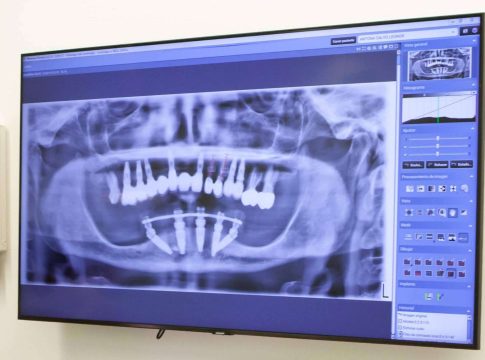

Prótesis fijas sobre implantes (All-on-4, All-on-6): Estas soluciones se basan en la colocación de un número reducido de implantes dentales estratégicamente en el hueso maxilar o mandibular. Sobre estos implantes, se coloca una prótesis fija completa que reemplaza todos los dientes perdidos. Esta técnica minimiza la necesidad de injertos óseos y permite una restauración rápida y efectiva de la función y estética dental.

Planificación digital y guías quirúrgicas: La tecnología digital ha revolucionado la implantología. Los escáneres 3D y los programas de planificación permiten una visualización detallada de la anatomía del paciente, lo que facilita la planificación precisa de la cirugía. Las guías quirúrgicas, fabricadas a medida, ayudan a colocar los implantes en la posición exacta planificada, mejorando la precisión y reduciendo el tiempo de cirugía.